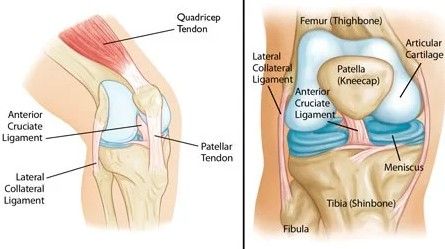

Diz artriti, diz eklemi yüzeyinde tahribata ve hasara yol açan kronik ve iltihaplı bir hastalıktır. Bu hastalıkta, diz kıkırdağı yüzeyindeki aşınma ve yıpranma derecesi artar ve eklemde ağrı, sertlik ve hareket kısıtlılığına neden olur. Diz osteoartritinin tedavisi genellikle semptomları yönetmeye, iltihabı azaltmaya ve eklem fonksiyonunu artırmaya odaklanır. Aşağıda, diz artriti semptomlarını yönetmede ve azaltmada faydalı olabilecek egzersizleri ve çözümleri inceleyeceğiz: